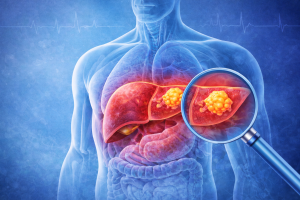

March 10, 2026Liver cancer is often referred to as a “silent disease” because it develops without noticeable symptoms in its early stages. The liver is a vital organ responsible for digestion, detoxification, and metabolism, and it can continue functioning even when affected.

How is liver cancer diagnosed?

Dr. Sharat Chandra Goteti employs a variety of modern diagnostic techniques:

Blood tests.

- Liver Function Tests (LFT)

- Alpha fetoprotein (AFP)

Imaging tests

- Ultrasound

- CT Scan/MRI